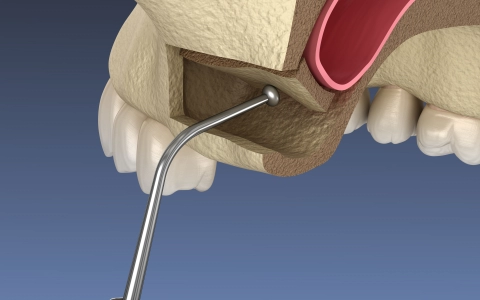

Sinus Lifting Tedavisi

Sinus lifting risksiz bir işlem değildir ama doğru hekim, doğru planlama ve uyumlu hasta üçlüsü ile yüksek başarı oranına sahiptir.